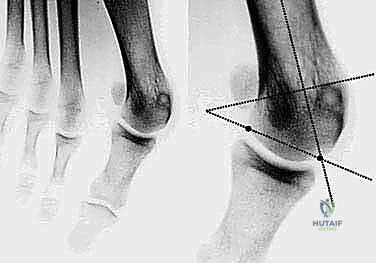

- القياسات الهندسية لزوايا القدم: يقوم الدكتور هطيف بقياس زوايا محددة لتحديد نوع الجراحة، أهمها:

- HVA (Hallux Valgus Angle): زاوية انحراف الإبهام (الطبيعي أقل من 15 درجة).

- IMA (Intermetatarsal Angle): الزاوية بين العظمة المشطية الأولى والثانية (الطبيعي أقل من 9 درجات).

- DMAA (Distal Metatarsal Articular Angle): زاوية سطح المفصل، وهي الزاوية الأهم التي تحدد الحاجة لتقنية "ش